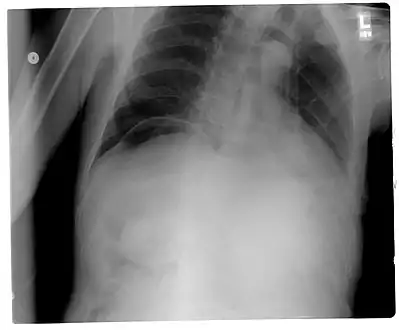

Another pneumoperitoneum on chest X-ray.